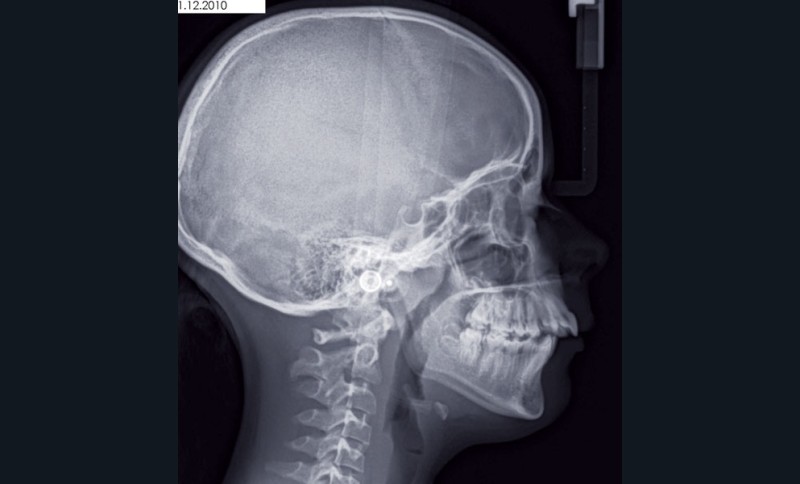

Son profil convexe s’inscrit dans un contexte de rétrognathie hyperdivergente associée à une proalvéolie et un encombrement maxillo-mandibulaire.

• Obtenir des rapports squelettiques de classe I par réponse de croissance mandibulaire.

La résolution de la classe II squelettique n’est aucunement recherchée au travers des extractions mais par une mécanique interarcade.